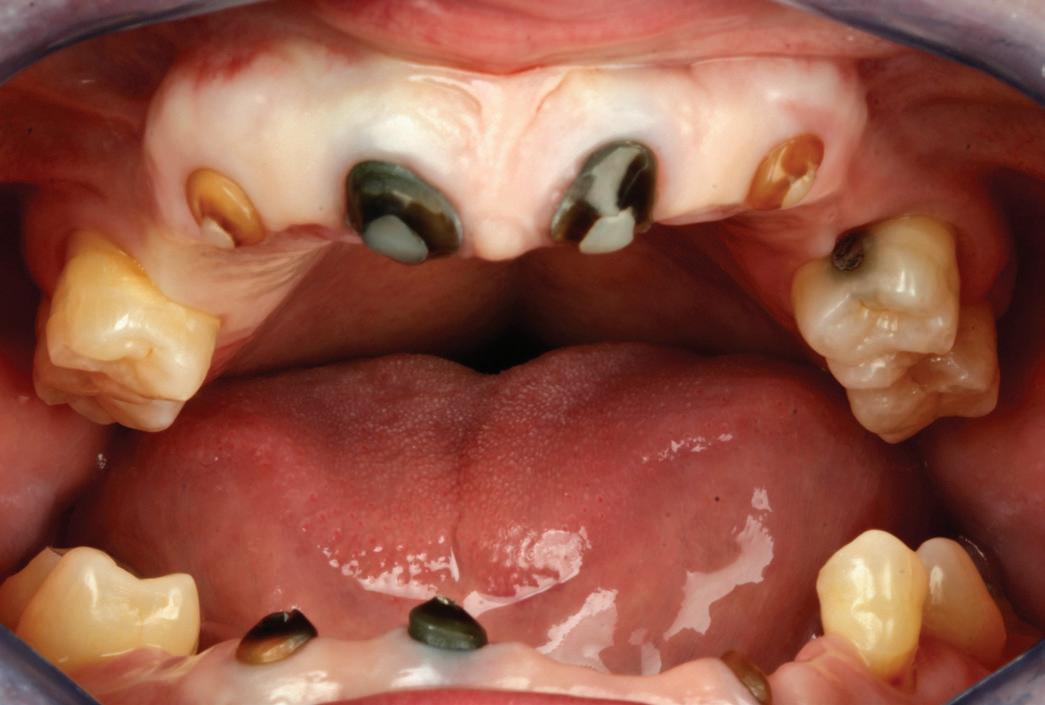

Un pacient caucazian în vârstă de 77 ani s-a prezentat la clinica autorului după cinci ani în care nu a fost la niciun control stomatologic. Examinarea clinică a arătat o pierdere semnificativă de os, parodontită cronică și multiple edentații care au destabilizat ocluzia. Pacientul a raportat sensibilitate la rece la nivelul primului molar drept inferior nr. 46, în special la ingerarea de lichide reci. Radiografia periapicală a confirmat constatările examenului clinic; în

plus, s-a detectat și prezența unei carii radiculare la nivelul rădăcinii distale a aceluiași molar, cu răspuns pozitiv la testul de sensibilitate (fig. 1-2).

Planul de tratament a început cu accent pe restabilirea sănătății parodontale. Într-o ședință ulterioară, odată cu îmbunătățirea stării parodonțiului, s-a efectuat restaurarea molarului nr. 46. Sub anestezie la Spina Spix pe partea dreaptă și

1. Situația clinică inițială.

2. Radiografia inițială.